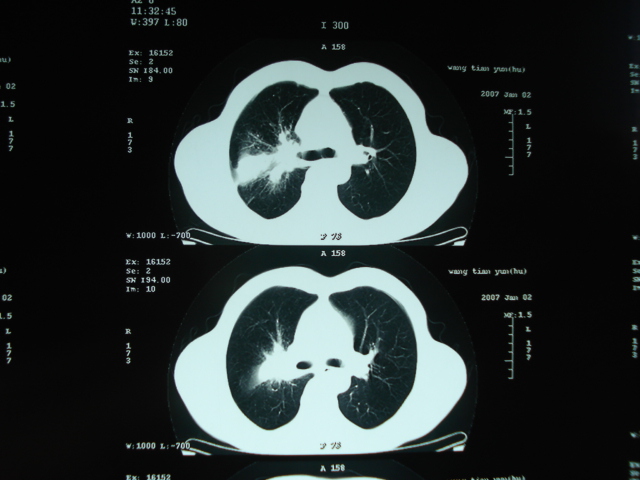

以下是引用狙击手在2007-4-18 20:17:00的发言:[br]原:2007/1/22号ct片:右肺上叶可见片状、云雾状高密度影,右肺上叶后段可见三角形高密度影,尖端指向肺门,右肺上叶后段支气管壁不规则增厚,管腔不规则增厚,纵隔未见肿大淋巴结.[br] 今ct:右肺上叶片状影增大,右肺上叶后段不张及右肺上叶后段支气管壁不规则增厚未见变化,右肺下叶背段支气管壁不规则增厚.[br] 如果考虑肺结核,但从临床证据看竟然没有一项支持肺结核,不知患者是否已经过正规抗结核治疗。没有的话,3个月了前后片看起来变化不大,似乎有不太符合肿瘤征象,不知患者是否抗炎治疗过,下叶支气管增粗还是要高度警惕,同意楼主意见,将常规病理,生化检查再做一遍。[br]

以下是引用狙击手在2007-4-18 20:17:00的发言:[br]原:2007/1/22号ct片:右肺上叶可见片状、云雾状高密度影,右肺上叶后段可见三角形高密度影,尖端指向肺门,右肺上叶后段支气管壁不规则增厚,管腔不规则增厚,纵隔未见肿大淋巴结.[br] 今ct:右肺上叶片状影增大,右肺上叶后段不张及右肺上叶后段支气管壁不规则增厚未见变化,右肺下叶背段支气管壁不规则增厚.[br] 如果考虑肺结核,但从临床证据看竟然没有一项支持肺结核,不知患者是否已经过正规抗结核治疗。没有的话,3个月了前后片看起来变化不大,似乎有不太符合肿瘤征象,不知患者是否抗炎治疗过,下叶支气管增粗还是要高度警惕,同意楼主意见,将常规病理,生化检查在做一遍。[br]